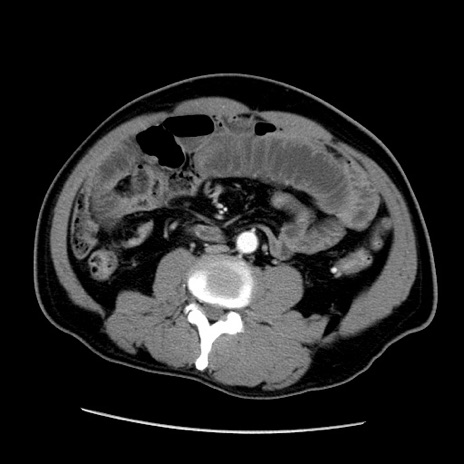

症例22(横断像)

【症例】50歳代男性

【主訴】腹痛

【現病歴】AVMからの被殻出血のため回復期リハ病棟入院中。 本日午後3時頃急に下腹部痛が出現した。

【既往歴】AVM、被殻出血、虫垂炎、高血圧

【身体所見】意識晴明、左半身不全麻痺、会話の理解は良好、36.5°C、腹部:膨隆、全体に板状硬、下腹部正中に圧痛点あり、反跳痛-、筋性防御不明、右下腹部にope scar

【データ】WBC 9400、CRP 0.06